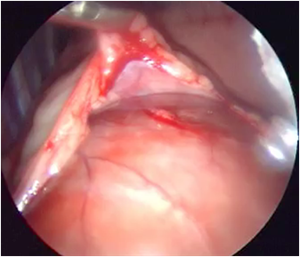

- Pericardial window

- Myocardic biopsy

- Lead and electrode positionning

- Controle pacing